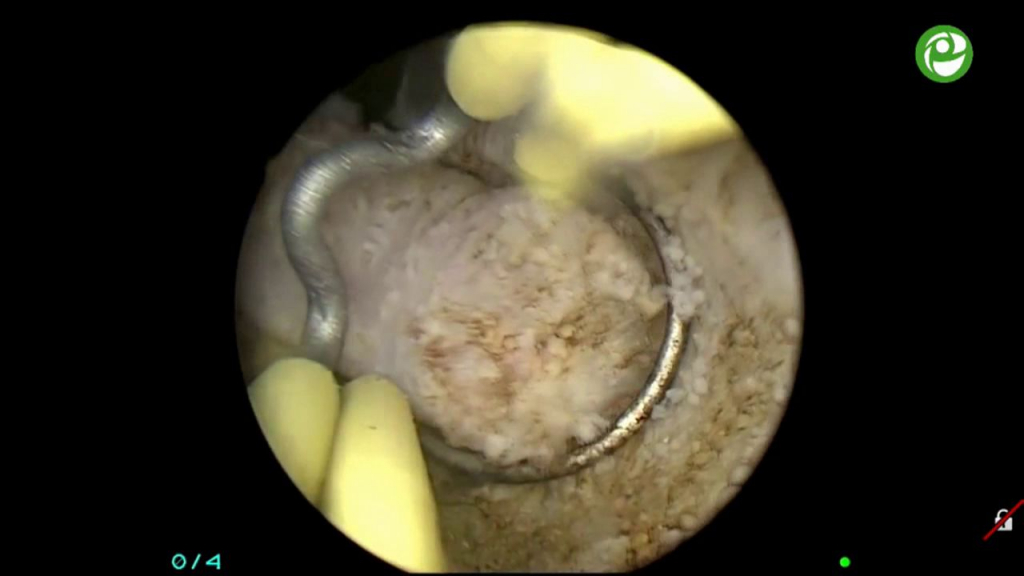

Операция "Биполярная ТУР простаты"

Операции на простате